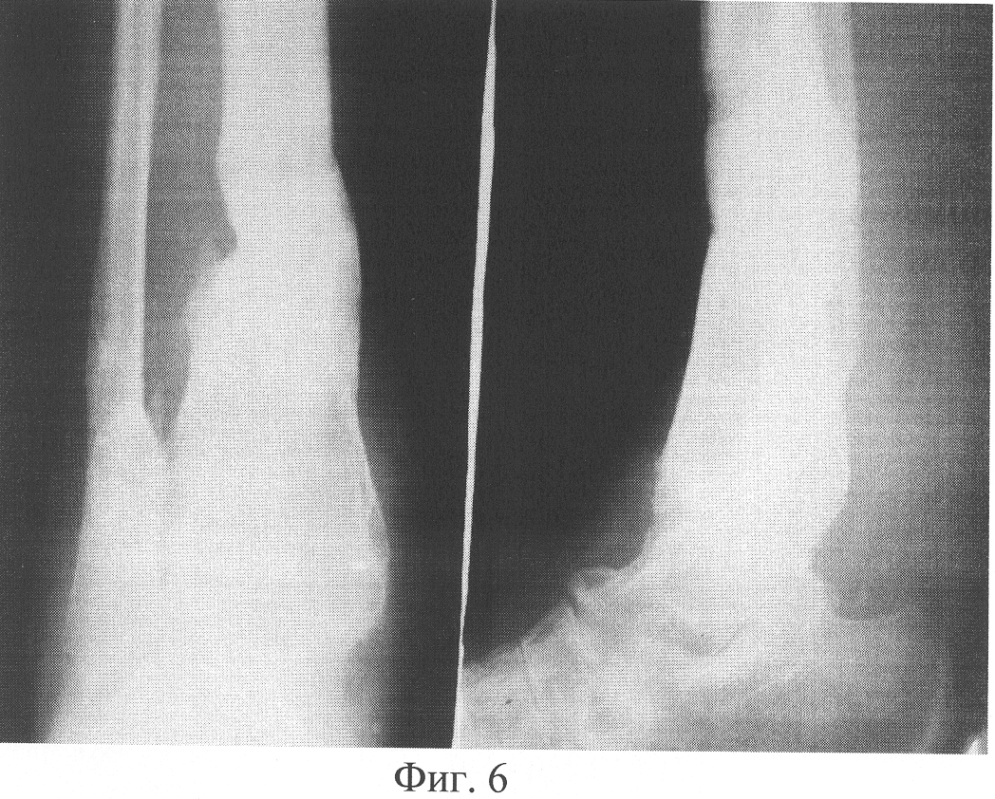

Пример 3. Больной Т., 19 лет, поступил через 745 дней с момента травмы с диагнозом «Посттравматический псевдоартроз нижней трети левой большеберцовой кости. Вальгусно-антекурвационная деформация нижней трети левой голени». Из анамнеза известно, что через 5 дней с момента получения травмы была произведена операция – остеосинтез нижней трети левой большеберцовой кости аппаратом Илизарова. В ходе лечения отмечались следующие жалобы: боли в левой нижней конечности, ограничение функции, возможность передвижения только с двумя дополнительньми опорами. Больной в течение 740 дней лечился с помощью вышеуказанного аппарата, при этом консолидации перелома не наступило. В амбулаторных условиях аппарат внешней фиксации был демонтирован. В результате Т. обратился в клинику травматологии и ортопедии. При проведении клинико-рентгенологического исследования был диагностирован посттравматический псевдоартроз нижней трети левой большеберцовой кости, вальгусно-антекурвационная деформация нижней трети левой голени. Рентгенограмма представлена на фигуре 5. Через 3 дня с момента поступления больному была произведена операция – остеосинтез левой голени аппаратом внешней фиксации спице-стержневого типа, остеотомия левой малоберцовой кости, кортикотомия костей левой голени в нижней трети. Деформация была устранена. После чего в асептичных условиях стерильным скальпелем в стерильном почкообразном лотке измельчили 5 пластин биоматериала аллоплант для склеропластики до размеров крошки 1×1 мм. В условиях операционной у больного осуществили забор крови из кубитальной вены в объеме 5 мл. Затем аутокровь в объеме 5 мл в асептичных условиях перелили в предварительно стерилизованный флакон, куда добавили измельченный биоматериал аллоплант для склеропластики. Место будущей инъекции обезболили 5 мл 0,5% раствора новокаина. Вышеназванные субстанции перемешали и набрали в одноразовый шприц для инъекций, снабженный иглой Гордеева с диаметром отверстия 2 мм, после чего произвели однократную инъекцию лекарственной взвеси в полном объеме в зону ложного сустава. Послеоперационный период протекал без осложнений. Консолидация достигнута через 90 дней (нормальные сроки сращения составляют 75-120 дней, в условиях отягощенного анамнеза – например, при ложном суставе, – затягиваются на неопределенный срок), что подтверждено клинически и рентгенологически. Рентгенограмма представлена на фигуре 6. Осложнений в процессе лечения не было. Получен хороший анатомо-функциональный результат лечения.